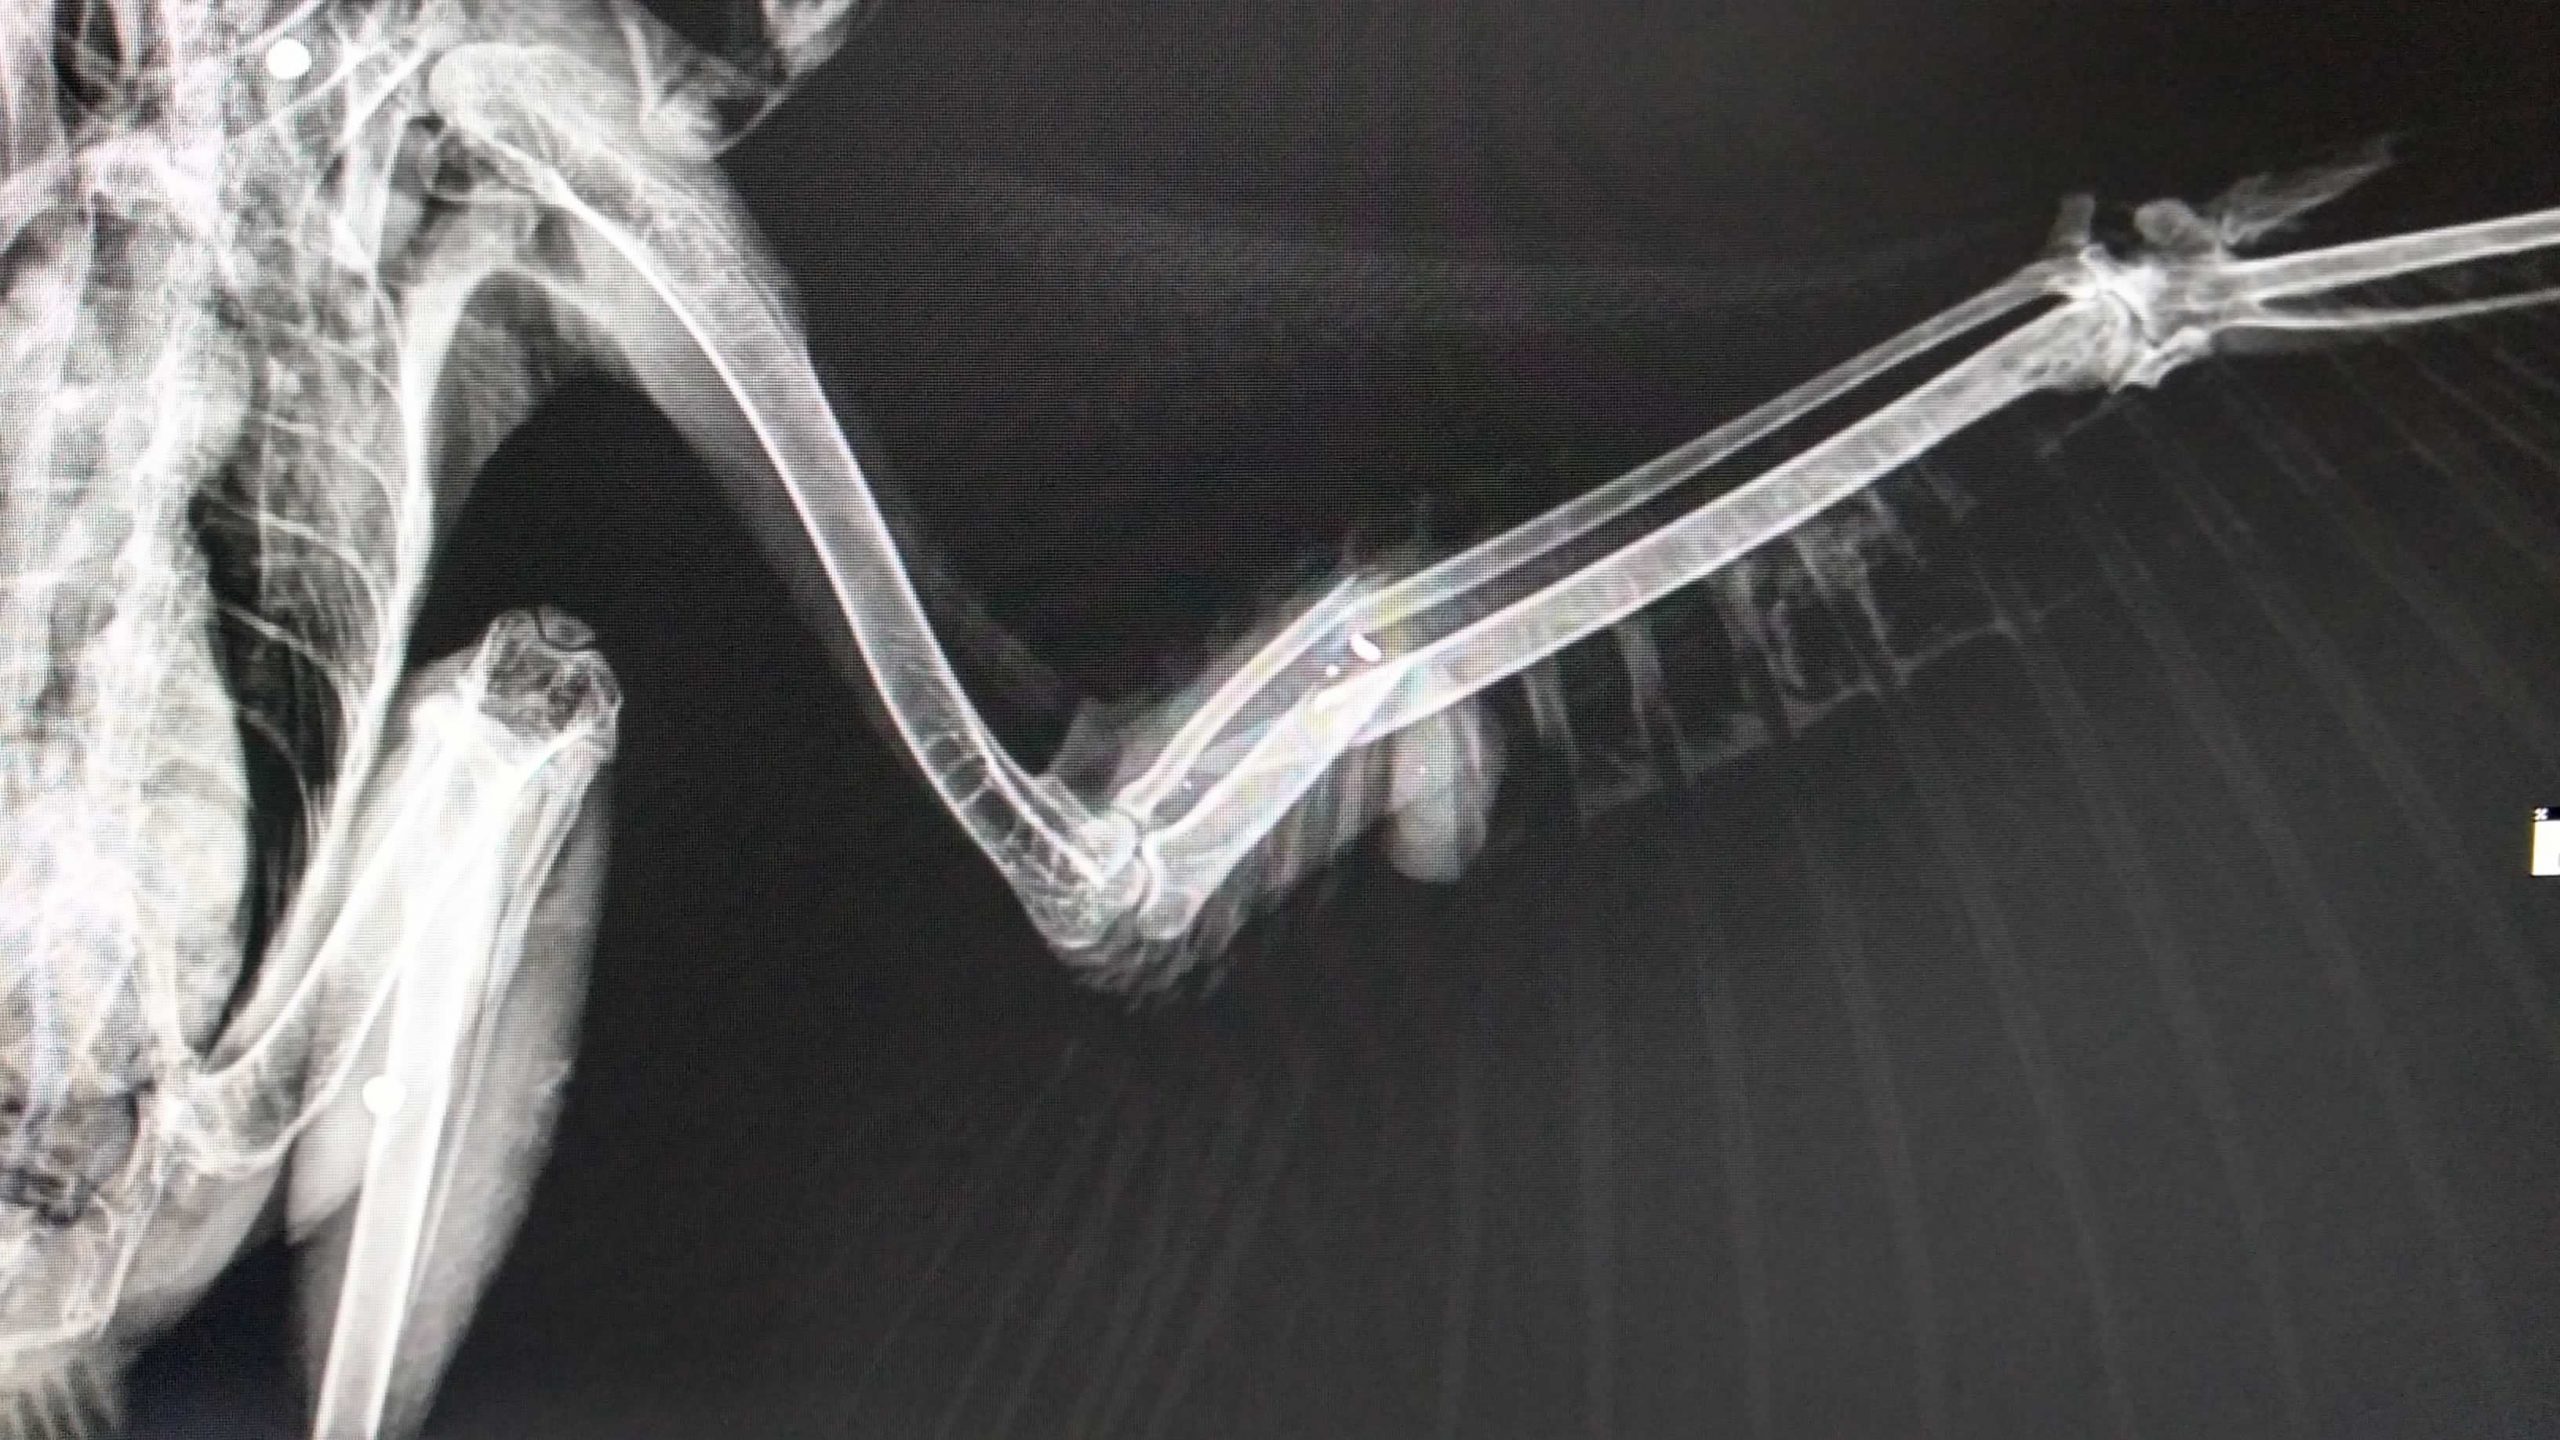

Esta ave ingresó al Centro de Atención y Valoración-CAV de Fauna Silvestre de la CAM gravemente herida en su ala izquierda. Luego de la valoración médica y la toma de radiografías, se evidenció que le habían disparado con perdigones.

Producto de este ataque, el águila presentaba varias fracturas en su extremidad alar y requirió ser intervenida quirúrgicamente, operación que se adelantó en conjunto entre la autoridad ambiental del Huila y la facultad de Medicina Veterinaria y Zootecnia de la universidad Corhuila.

“En el momento de la valoración que incluyó la toma de radiografías, los profesionales diagnosticaron que el ave presentaba cuatro impactos por perdigones en diferentes áreas de su cuerpo, y registraba una fractura cerrada de radio y cubito en su ala izquierda”, explicó Osiris Peralta Ardila, profesional de la CAM.